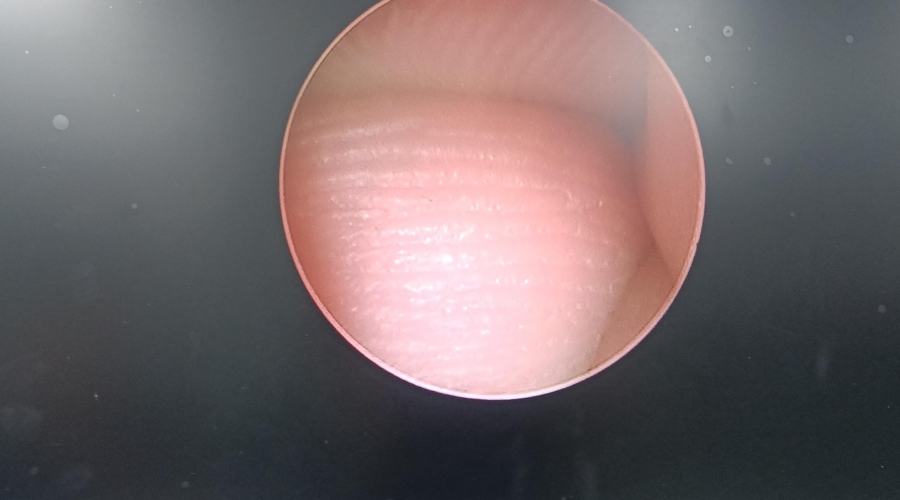

以下為維修案例分析及故障實(shí)拍:

故障內(nèi)容圖像模糊,棒透鏡破碎。

維修方案更換棒透鏡 ,校對(duì)圖像,內(nèi)窺鏡抗震蕩抗沖擊性能測(cè)試,內(nèi)窺鏡密封性性能檢測(cè);內(nèi)窺鏡抗震蕩性能測(cè)試,內(nèi)窺鏡冷熱沖擊性能檢測(cè)。